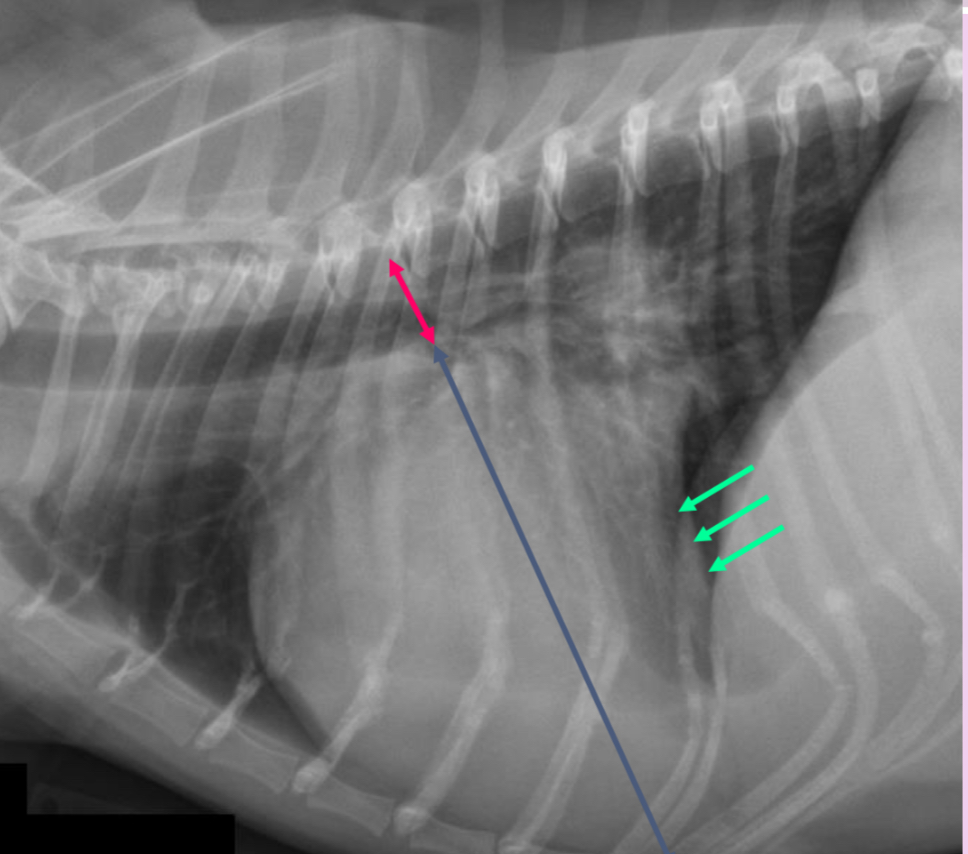

3 features of LAE on lateral

-dorsal displacement of main stem bronchi by a hunchback bump

-increased cd.dorsal cardiac border

-loss of cd.cardiac waist - straightening of cd.cardiac margin

What part of the heart is enlarged

LAE

3 features of LAE on DV

-double opacity sign

-separation of main stem bronchi

-LA bulge at 2:30-3 o’clock